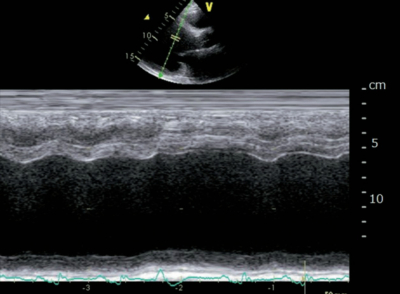

体温 36.4 ℃。脈拍 112/分、整。血圧 152/82 mmHg。呼吸数 20/分。SpO2 95 %(room air)。両下胸部にcoarse cracklesを聴取する。胸部エックス線写真を別に示す。心電図は洞性頻脈でST-T変化を認めない。心エコー図を別に示す。